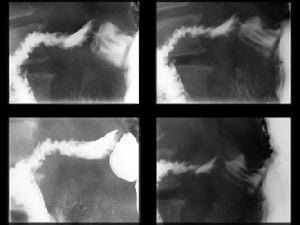

Noticias y Articulos Tránsito esofagogastroduodenal (E.G.D.) – Parte II 21 junio, 2012 Tidito Imágenes Transito Esofagogastroduodenal (E.G.D.) Seriadas Bulbares Duodeno en Anteroposterior